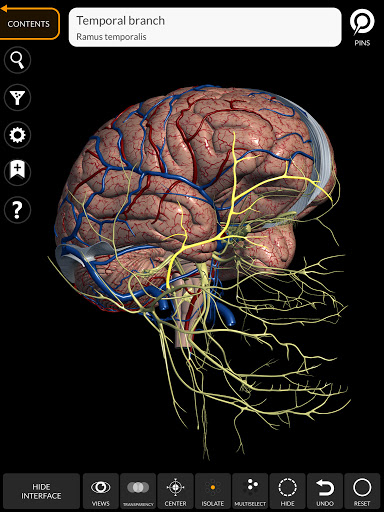

Grâce à une interface simple et intuitive, il est possible d'observer chaque structure anatomique sous n'importe quel angle.

Les modèles anatomiques 3D sont particulièrement détaillés et avec des textures jusqu'à une résolution de 4k.

• Système nerveux

• Faites pivoter et zoomez chaque modèle dans l'espace 3D

• Option pour masquer ou isoler un ou plusieurs modèles sélectionnés

• Fonction de transparence

• En sélectionnant un modèle ou une épingle, le terme anatomique associé apparaît